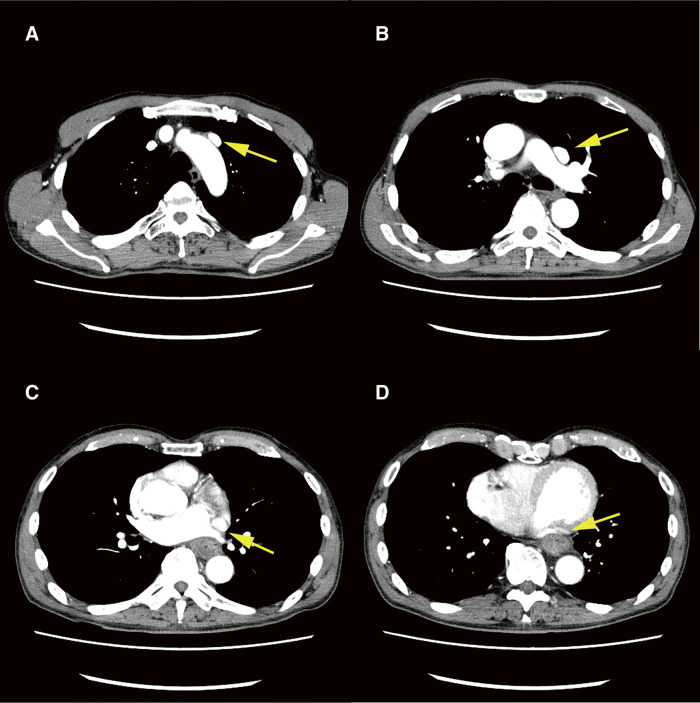

Case presentation: A 75-year-old male patient required a central venous port for chemotherapy and radiation therapy for mid-thoracic esophageal cancer. Preoperative computed tomography images revealed that the PLSVC ran ventrally to the aortic and left pulmonary arteries, directly communicating with the right atrium. A peripherally inserted central catheter (PICC) port was planned. The catheter tip of the PICC port was placed within the left superior vena cava instead of the more common right superior vena cava, because the appropriate vessels could not be identified in the right upper arm. This anomaly necessitated a review of findings on the preoperative imaging and underscored the importance of early detection through echocardiography and radiographic guidance to prevent procedural complications. Reconstructed three-dimensional images and radiography-guided catheterization support the navigation of PICC port insertion.